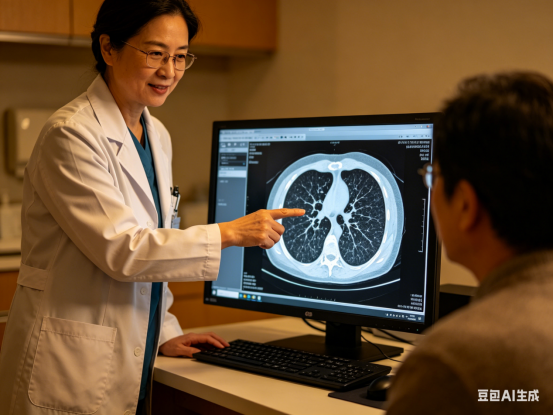

一、那么,通过CT检查能够发现肺肿瘤病情吗?

成都东区中医肿瘤医院/成华东区医院肿瘤科江学文主任讲:一般来说,在怀疑自己发生肺肿瘤的时候比较好的方式就是进行肺部CT检查,因为相对于普通的胸片检查来说,CT所呈现出来的清晰度更高。而且对比度会更好,它能够更加清楚的发现恢复中一些微小的病灶,还能够帮助患者知道肺肿瘤的具体病变情况以及病变的部位。因此对于一些长期吸烟以及有肺肿瘤家族史的风险人群,要定期进行肺部CT检查来排查肿瘤病情。